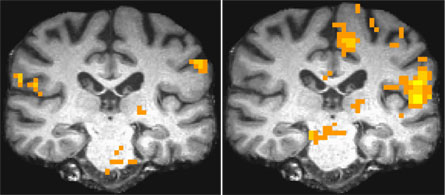

In healthy veterans, appropriate parts of the brain lit up as they thought, reasoned, viewed – even experienced extremes of temperature. But in men suffering from Gulf War Illness, Haley says, “a different part would often light up as their brain attempted to work around its damage.”

Affected areas of the brain in each test varied. The thalamus, for example, is involved in attention and inhibition, Briggs explains. “It is activated differently in syndrome two versus controls,” he notes. Not surprisingly, people with that particular syndrome have problems with those traits. The researchers also correlated what combinations of areas in the brain respond in concert during particular tasks. And sometimes, the collection of brain locales that lit up in sick vets differed markedly from those in healthy vets (see images above).